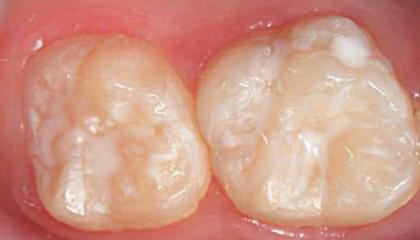

• Fissure sealants2

Fissure sealants AFTER